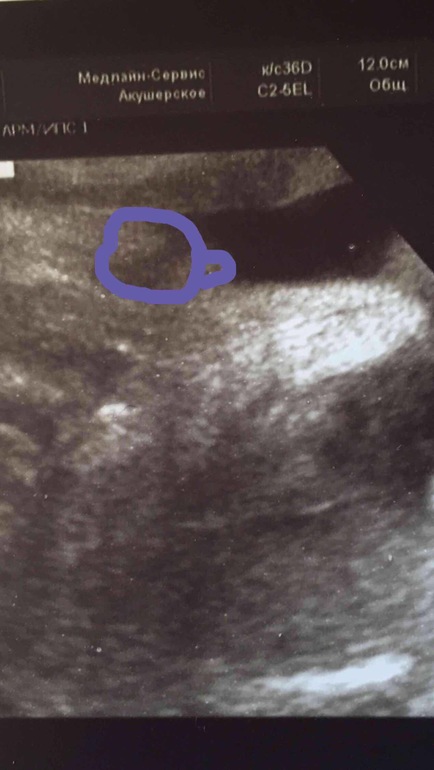

УЗИ в 30 недель

ДругоеСегодня на УЗИ сказали похоже девочка. А вы что скажете? Разве похоже на девочку? Крестиком отметил узист то самое.

это наш писюн мальчуковый на 22 неделе. А у вас...конечно я ж не спец...клитор может быть такой большой на 30 неделе? Может вполне и пацан, просто не под тем углом)) сходите отдельно на УЗИ , пол посмотрите!!!))И пишите сдесь, оч интересно!!!)

я девочку вижу...у меня с сыном в 14 недель отросточек побольше был